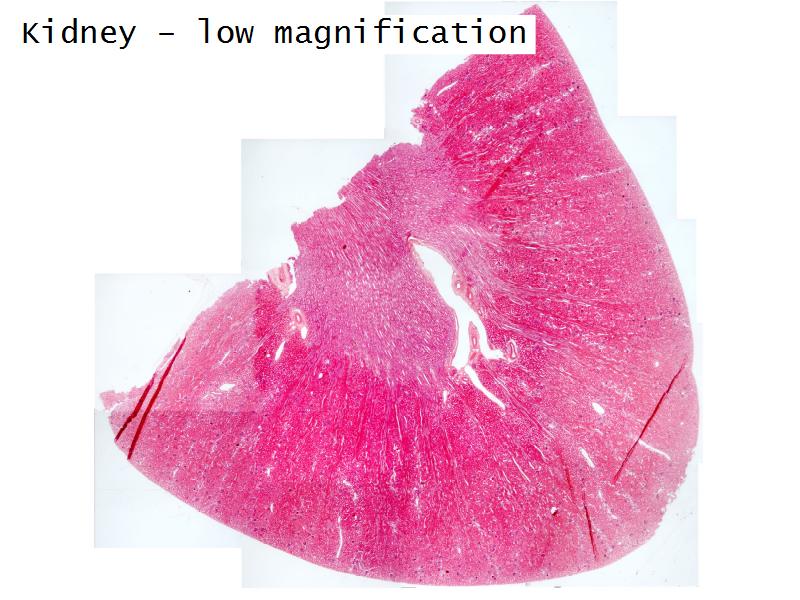

- Kidney

- Slide 76: Kidney